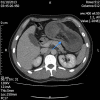

Abdominal pain secondary to intussusception is a common presentation in the paediatric population but rare in adults. Diagnosis is often difficult due to non-specific signs and symptoms. Adult intussusception presents more insidiously with intermittent abdominal pain and signs and symptoms of an acute abdomen are rare. In children, the aetiological factor is usually idiopathic, whereas intussusception in adults is more commonly due to an underlying pathology giving rise to a lead point. Consequently the treatment of choice is different-while it is supportive in children, surgical management is typically indicated in adults. In addition, the causes of a lead point precipitating adult intussusception are different depending on whether they arise from the small or large bowel. This report presents a case of jejunal intussusception in a 30-year-old man with a characteristic CT scan who required exploratory laparotomy and small bowel resection.